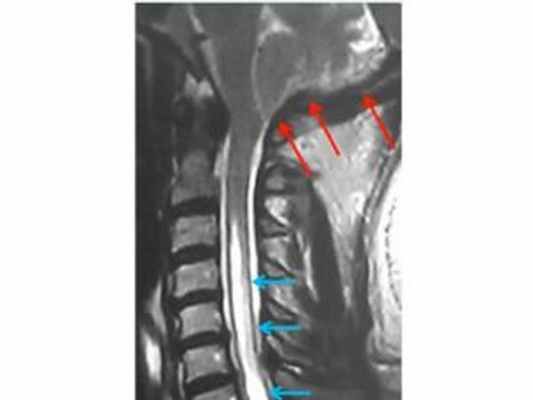

МРТ изображение (T2-взвешенное изображение) кранио-вертебрального перехода и шейного отдела позвоночника. Определяется комбинированный порок развития (аномалия Киари и платибазия), который привел к нарушению циркуляции ликвора в области большой затылочной цистерны, в результате чего развилась сирингомиелия (синие стрелки).